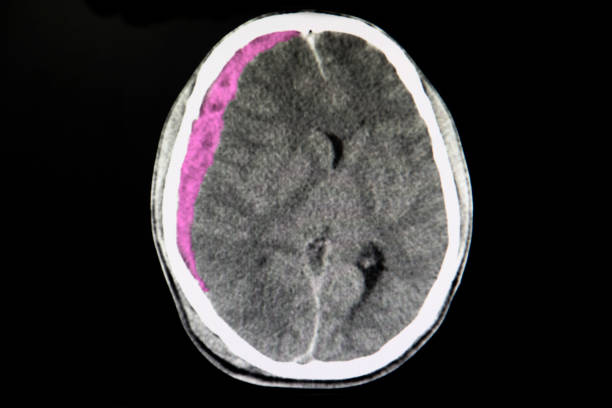

뇌출혈은 뇌안에 있는 혈관에서 출혈이 발생하여 뇌조직이 손상을 입는 질환이며, 중증의 뇌혈관질환 중 하나입니다. 일반적으로 고혈압, 동맥류, 혈관 기형, 혈전 등의 이유로 혈관이 파열하거나 뚫리면서 발생합니다.

고혈압은 뇌출혈을 일으키는 가장 일반적인 원인 중 하나입니다. 고혈압은 혈관벽을 약화시켜 혈관이 파열하기 쉽게 만들기 때문입니다. 또한, 혈관에 생긴 약간의 이상증상이나 동맥류, 혈관 기형 등도 뇌출혈의 원인이 될 수 있습니다.

뇌출혈은 갑작스러운 발작, 의식 잃음, 경련, 혼란, 언어 장애, 편마비 등의 증상을 일으키며, 이러한 증상이 발생하면 즉시 의료진의 진료를 받아야 합니다. 뇌출혈은 치료가 지연되면 심각한 후유증을 일으킬 수 있으므로, 조기 발견과 적절한 치료가 필요하기 때문에 이번 시간에는 뇌출혈 전조 증상에 대해 자세히 알아보겠습니다.